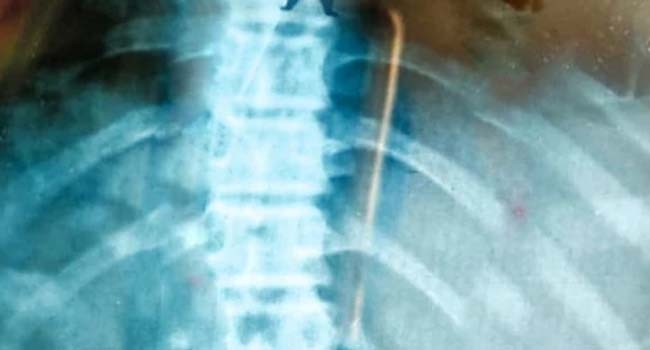

എക്സ്റേ എടുത്തപ്പോള് മൊട്ടുസൂചി ഉള്ളില് കുടുങ്ങിയ നിലയിലായിരുന്നു. ഇത് പുറത്തെടുക്കാന് ശ്രമിച്ചെങ്കിലും കഴിഞ്ഞില്ല. മറ്റ് രണ്ട് സ്വകാര്യ ആശുപത്രികളിലും കയറിയിറങ്ങിയെങ്കിലും മൊട്ടുസൂചി പുറത്തെടുക്കാനായില്ല. ഈ സമയമൊക്കെ അസഹനീയ വേദന തിന്നുകയായിരുന്നു ഷബ്ന. ഒടുവില് അര്ധരാത്രിയോടെ ആസ്റ്റര് മെഡ്സിറ്റി ആശുപത്രിയിലേക്കു മാറ്റി.

അവിടെ എക്സ്റേയില് ആമാശയത്തില് ഭക്ഷണത്തിന്റെ ഇടയില് കുടുങ്ങിയ നിലയില് മൊട്ടുസൂചി കണ്ടെത്തി. തിങ്കളാഴ്ച രാവിലെയോടെയാണ് എന്ഡോസ്കോപ്പി വഴി മൊട്ടുസൂചി പുറത്തെടുത്തത്. ഒരു മണിക്കൂര് എടുത്തു എന്ഡോസ്കോപ്പി ശസ്ത്രക്രിയയ്ക്ക്. ആരോഗ്യനില വീണ്ടെടുത്ത പെണ്കുട്ടി വൈകാതെ ആശുപത്രിയില് നിന്ന് ഡിസ്ചാര്ജായി.